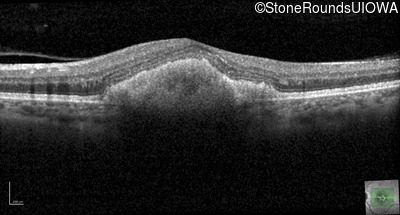

Age at visit: 36 years

Diagnosis & molecular findings

Disease Gene Allele 1 variant(s) Allele 2 variant(s) Inheritance mode

Pattern Dystrophy PRPH2 Gly167Asp GGC>GAC   AD